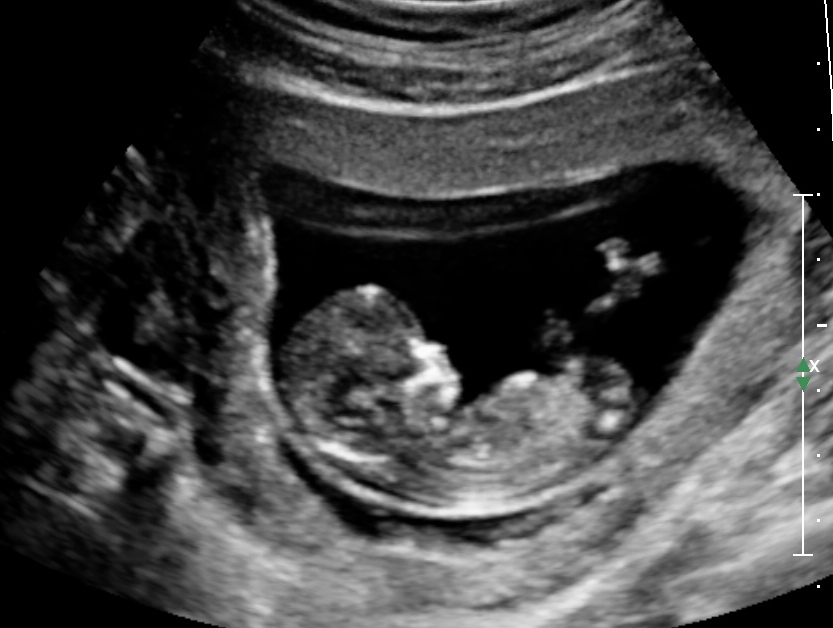

Any chance this could be a girl!? lol hoping for a girl but will be blessed either way.

Do you any of see the nub? With skull theory i would say boy- but how accurate do you think that is?

Maaaybe boy based on 2nd pic nub? I don't believe in skull theory.

Maybe boy, but still could be girl, not the best pics

Second pic looks quite boyish.